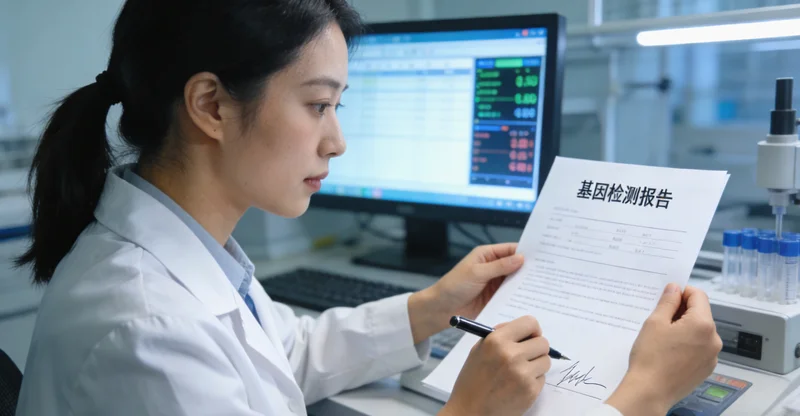

这是最后提一嘴,也是最重要的一步。基因检测报告不是“判决书”,而是“决策参考书”。它必须回到临床医生手里,由医生结合您的具体影像、病理、身体状况乃至家庭情况,做出综合判断。报告可能会提示:靶向药物有哪些选择?预后大概如何?家属的筛查建议是什么?

好的检测机构,会提供专业的报告解读服务。例如 万核基因 提供的服务中,就包含了对关键结果的清晰注解,并且其医学团队可以应临床医生要求,提供更深入的技术解读支持,帮助临江的医生和患者家庭更好地理解并运用这份报告。记住,您永远不是一个人在战斗,检测机构、临床医生和您及您的家庭,是一个共同决策的团队。

▲ 医生与患者共同查看分析基因检测报告(示意图)